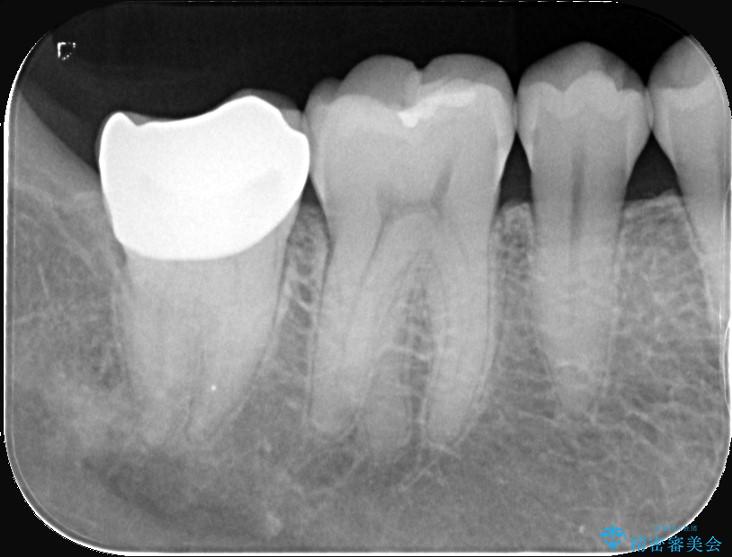

- 頬側に大きな虫歯があり、神経に達している可能性が高かったため、虫歯除去時に神経が出た場合はVPTを提案しました。

虫歯が神経まで達していましたが、術前の検査でVPTの適応と診断をしていたので、ラバーダムシートを装着しVPTを行いました。

経過も良好で、痛みも無く神経を残すことが出来ました。